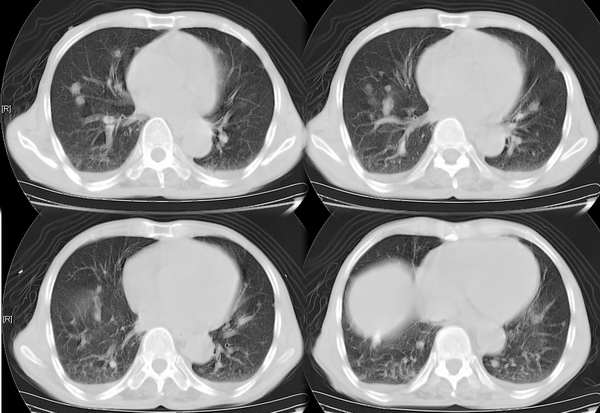

右颈部巨大软组织肿块影,范围较广,上至下颌角,下至颈静脉切迹。其最大层面位于右侧甲状腺区。肿块密度不均,其中有坏死液化区和班片状钙影,增强扫描见肿块实质区有强化。邻近结构挤压移位,部分结构侵蚀破坏,右侧多个颈深淋巴结肿大。两肺弥漫分布小结节影,以胸膜下为主,其大小不等,边缘光整。右侧胸壁亦见软组织结节影,纵隔多个淋巴结肿大及两侧锁骨上淋巴结肿大。

意见:右侧甲状腺癌并两肺、胸壁、纵隔淋巴结、颈深淋巴结、锁骨上淋巴结等广泛转移。